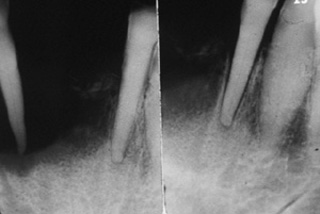

Reabsorción ósea Una radiografía de este

paciente de 62 años de edad descubrió una reabsorción ósea que no es

típica de la enfermedad periodontal. Esto debe alertar de una

enfermedad seria y debe indicarse la biopsia. Desgraciadamente, en

este caso el odontólogo realizo las exodoncias y al ver que las heridas

no cicatrizaban, decide realizar la interconsulta al especialista. |

Crecimiento post exodoncia El área

de las exodoncias no cicatrizó (ver imagen anterior); y tres

semanas después había un crecimiento exofítico de apariencia

granular. |